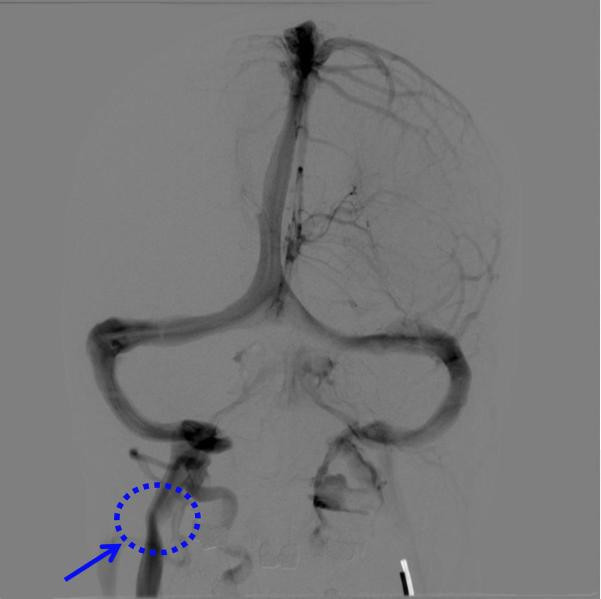

为进一步精确评估头颈静脉血液回流情况,在该院神经外科主任李明昌西宾、脑血管病区主任徐海涛西宾的诱骗下,丁锐副主任医生领衔的头颈静脉疾病团队为周女士现实全脑血管造影(DSA)查验。查验进一步阐述其右侧颈内静脉存在明显受压与狭隘,同期撤销了其他头颈部血管疾病。

脑DSA查验透露右侧颈内静脉狭隘(蓝色箭头所示)

过程详备的术前沟通、多学科诊断,团队最终明确诊断周女士为“脑鸣详细征”,其根底病因是颈内静脉受到外源性骨性压迫,尤以寰椎横突骨质压迫最为权臣。